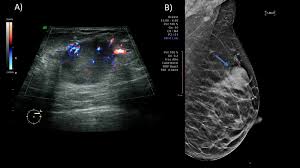

On ultrasound it will be hypoechoic with spiculations radiating away from the nipple. Radiographic features ultrasound malignant characteristics (with positive predictive values) Ultrasound imaging allows better evaluation of the status of the axillary lymph nodes in patients with ibc, an important step in determining extent of disease prior to initiation of chemotherapy. Is the abnormal enlargement of rudimentary male breast tissue. You might get a breast ultrasound: Breast cancer is among the most common causes of cancer deaths today, coming fifth after lung, stomach, liver and colon cancers. Many cancers are not visible on ultrasound. Breast cancer usually makes or presents as a mass or tumor or a lump. This type of cancer also changes the appearance of your breasts. Papillary dcis, a special variant, will show up as matter within the ducts, like a clog within a pipe. It is the most common cause of cancer death in women. in 2005 alone, 519 000 deaths were recorded due to breast cancer. this means that one in every 100 deaths worldwide and almost one in every 15 cancer deaths were due to breast cancer. Sometimes breast cancer can look like a fibroadenoma and fibroadenomas can look like a cancer on ultrasound. Many calcifications seen on mammography cannot be seen on ultrasound.

Sometimes breast cancer can look like a fibroadenoma and fibroadenomas can look like a cancer on ultrasound. Some early breast cancers only show up as calcifications on mammography. Breast cancer usually makes or presents as a mass or tumor or a lump. Rather, the right breast is seen as smaller than the left breast. On ultrasound, a breast cancer tumor is often seen as hypoechoic, has irregular borders, and may appear spiculated.

You might not need any further tests if everything looks normal. It can help your healthcare provider find breast problems. When is breast ultrasound used? If your breast tissue is too dense for a mammogram. This test is often used when a change has been seen on a mammogram or when a change is felt. Papillary dcis, a special variant, will show up as matter within the ducts, like a clog within a pipe. You may notice dimpling or pitting, and the skin on your breast. On ultrasound, a breast cancer tumor is often seen as hypoechoic, has irregular borders, and may appear spiculated. This breast cancer ultrasound image shows changes related to breast cancer that are not seen as microcalcifications or a mass or lump. Some early breast cancers only show up as calcifications on mammography. If a solid lump shows on the scan you might need to have. A rash isn't the only visual symptom of inflammatory breast cancer. Ultrasound is frequently used to evaluate breast abnormalities that are found with screening mammography or diagnostic mammography or during a physician performed clinical breast exam.ultrasound allows significant freedom in obtaining images of the.

Breast ultrasound is an imaging test that uses sound waves to look at the inside of your breasts. Ultrasounds are usually quick and most don't require special preparation. If your breast tissue is too dense for a mammogram. When is breast ultrasound used? Not all suspicious breast lesions will direct in appearance and ultrasound diagnosis. This high amount of echo results in a bright white spot appearing on the ultrasound image. You can get dressed straight after the ultrasound. Ibc is a rapidly progressive, aggressive form of breast cancer associated with a low overall survival rate. On ultrasound, a breast cancer tumor is often seen as hypoechoic, has irregular borders, and may appear spiculated. In the table the differences in ultrasound appearances are listed. Is the abnormal enlargement of rudimentary male breast tissue. This test is often used when a change has been seen on a mammogram or when a change is felt. Breast cancer usually makes or presents as a mass or tumor or a lump.